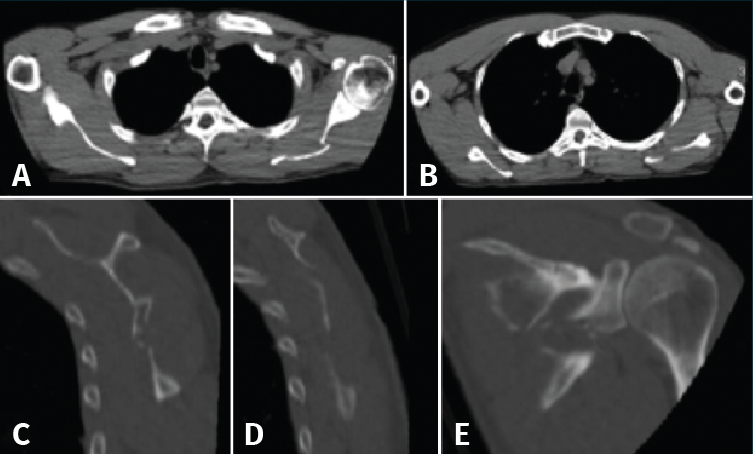

Figura 4. A y B: corte axial; C y D: sagital; E: coronal de tomografía computarizada (TC).

Tras la realización del estudio de imagen obtuvimos unas medidas de 64 mm para el offset del borde lateral, un ángulo glenopolar de 27,5°, una angulación de la deformidad correspondiente a 12,9° (Figura 6) y, por último, una superficie articular conservada íntegramente, visualizada en los cortes y en la reconstrucción tridimensional de la TC.